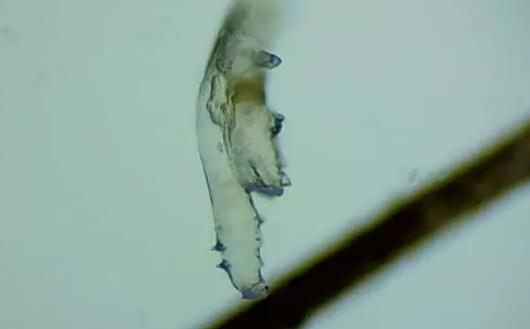

蠕形螨性睑缘炎

蠕形螨性睑缘炎.jpg

随着年龄增长,眼睛寄生有蠕形螨的几率也会逐渐增加,60、70岁左右的人群感染螨虫的几率更是接近99%。蠕形螨会引起蠕形螨性睑缘炎,患者会出现眼痒、异物感、眼干、睑缘充血、鳞屑、睫毛根部袖套状分泌物及睫毛脱落等典型表现,严重者可并发结膜及角膜病变。